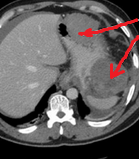

Red arrows – Rectal stromal tumor. Multiple liver metastases (Courtesy Dr. V. Penopoulos)